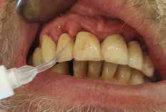

Patientensituation nach erfolgter Therapie mittels Metronidazol, CHX Chips, aPDT und anderen Maßnahmen nach dem 3. Recall

Applikation des OXYSAFE Gels in situ Patientensituation 3 Wochen nach Beginn der Sauerstofftherapie mittels OXYSAFE

Fallbericht

Ein 55-jähriger Patient kommt zur ersten Untersuchung in die Klinik der Abteilung für Parodon tologie des Klinischen Krankenhauses Zagreb. Er ist Raucher und hat keine systemischen Erkran kungen. Die Begutachtung des Orthopantomogramms und klinische Untersuchung weisen auf eine Parodontitis hin.

VorherNachher

Beispielhaft nun die Anwendug von OXYSAFE am Frontzahn

11. Die Sondierungstiefe beträgt sowohl mesial als auch distal 7 mm an Zahn 11 und es liegt eine Blutung vor. Es liegt ein vertikaler Knochenverlust vor.